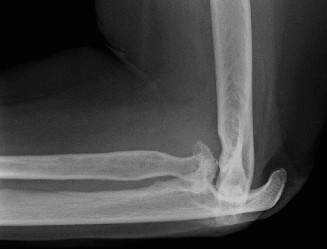

Understand common complications associated with performing surgery for scapulothoracic bursitis? CASE 33 A 42-year-old female presents to the office for follow up after sustaining a minimally displaced radial head fracture 3 months prior. She states she was initially treated in long-arm splint by the ER and did not follow up with an orthopaedic surgeon until now. Per her report, she removed the splint 4 weeks after the injury, but did not move her elbow due to pain. She now has no pain but is unable to reach that hand to her face or head. The remaining history is significant for previous ulnar nerve surgery for which she is unable to provide details. On physical examination, her upper extremity is normal except for limited flexion/extension, measured to be 80 to 50 degrees by goniometer. In addition, she has a well-healed surgical incision about the medial elbow, consistent with a previous surgery on her ulnar nerve. Her images are shown (Figs. 2–82 to 2–84).

Figure 2–82

Figure 2–83

Figure 2–84

What is the diagnosis?

- Early post-traumatic intrinsic joint contracture

- Late post-traumatic extrinsic joint contracture

- Late combined post-traumatic joint contracture

- Early combined post-traumatic joint contracture

Discussion

The correct answer is (A). Classification of post-traumatic elbow stiffness allows for better understanding of the disease and allows the clinician to treat the underlying cause of the joint contracture. Intrinsic causes include: any problem within the joint such as incongruency, loose bodies, or severe osteoarthritis. Extrinsic causes include capsular tightness, muscle contracture, heterotopic ossification, and skin contractures. Early is defined as within 6 months of the injury while late is considered to be greater than 6 months after the injury. Patients that present in the early time frame have a significantly better chance at having a good result both from nonoperative and operative treatment.